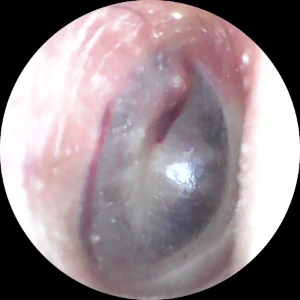

< (좌) 프렌젤 후, (우) BTV로 42.4m 다녀온 후 >

위 사진은 다이빙 후 귀내시경으로 촬영한 고막 상태를 보여줍니다. 왼쪽 사진은 프렌젤 후 촬영한 것으로, 고막 테두리와 망치뼈 부분이 충혈된 모습을 확인할 수 있습니다. 반면, 오른쪽 사진은 BTV로 42.4m 다녀온 후 촬영한 것입니다. 고막이 스트레스를 받지 않고 깨끗한 상태를 유지하고 있음을 알 수 있습니다. BTV로 40m를 넘게 가더라도 고막에 손상을 입을 가능성은 거의 없습니다.